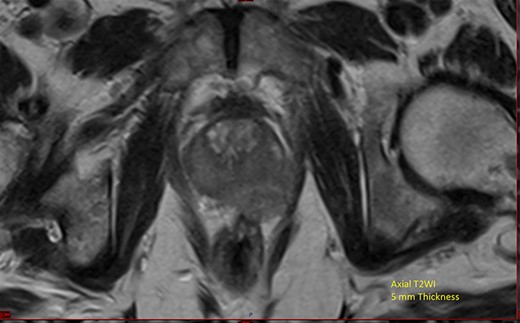

He underwent computerized tomography of the thorax, abdomen and pelvis, which showed lobular enlargement of the prostate with enlarged pelvic, para-aortic and cervical lymph nodes. Prostate-specific antigen (PSA) was elevated at 139 ng/ml. Magnetic resonance imaging (MRI) of the prostate showed extensive local disease (Fig. 1). Nuclear medicine bone scan revealed multiple sclerotic bony metastases.